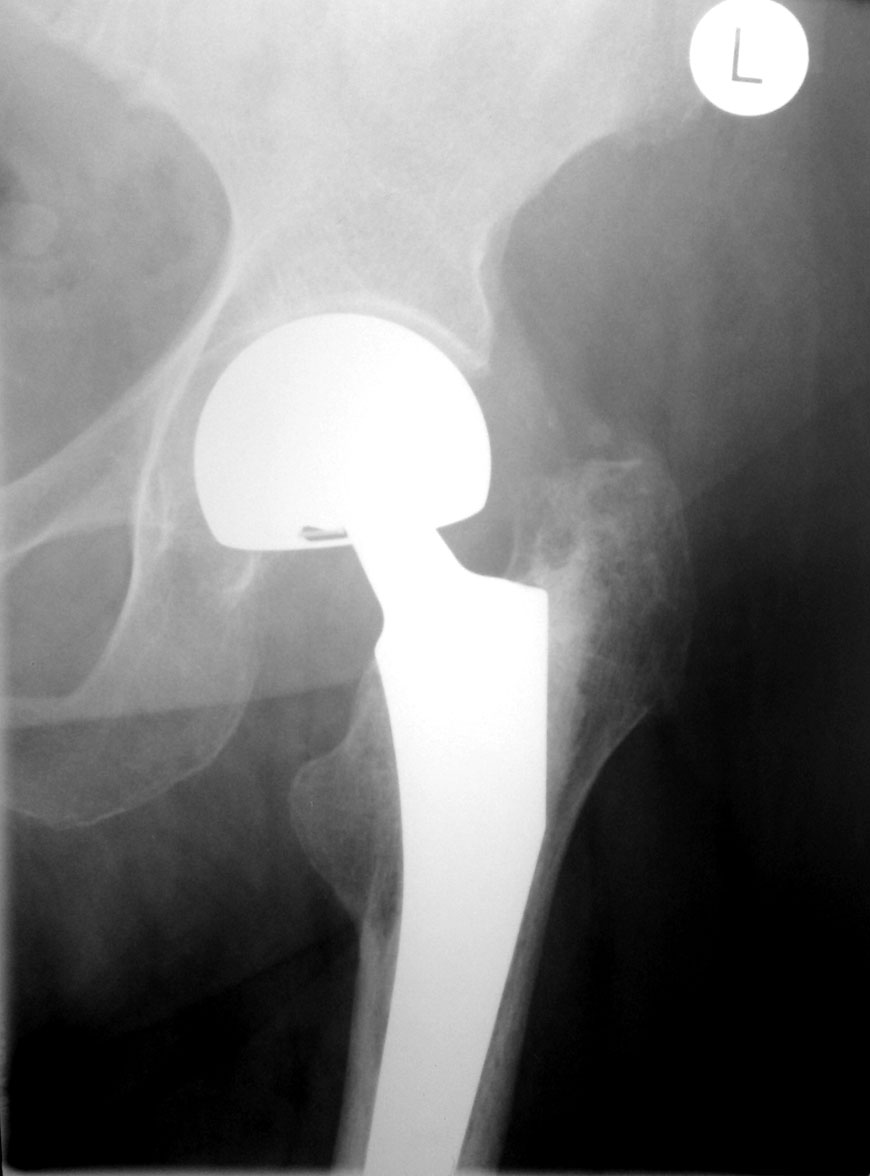

Как оценят коллеги состояние этого сустава? Возраст 77 лет, пол женский. Операция 8 мес назад.

Угол наклона чаши вертлужной впадины стремится к нулю... Расстояние от края чаши до костной основы впадины должна быть меньше 2 мм, но контур кости ровный и четкий.

Отведение вообще возможно? Протез головки бедра расположен эксцентрично, но рановато для износа полиэтилена, наверное. Нужен послеоперационный снимок для оценки динамики.

Ножка протеза беспокойства не вызывает.

По положению компонентов претензий нет. Смущает приведение в т/б суставе, но скорее всего лаборант ногу не отвел, а вообще приводяще-сгибательная контрактура у пожилых пациентов обычное дело.

Вероятно, стрелочками, которыми я просил отметить признаки биполярности протеза, следовало бы отметить контур и субхондральные слои вертлужной впадины, на которых нет признаков ятрогенной деструкции (когда впадина "вычищается" абразивом) - характерного неравномерного остеосклероза?

Признак биполярности я усматриваю со стороны основания «головки»: угадывается вложенность малой сферы в большую. Подробности по ссылке. Это только моё частное мнение  —  3D-представление и я не Источник.